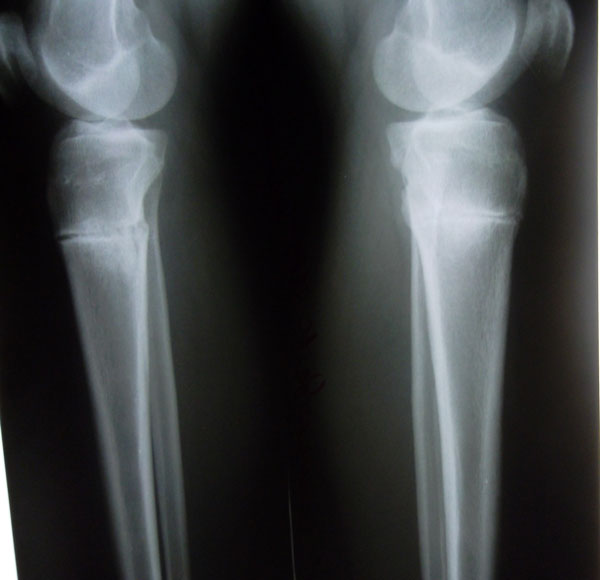

Результат

Рентгеновские снимки.

Вложения

SAM_0774.jpg

SAM_0765.jpg